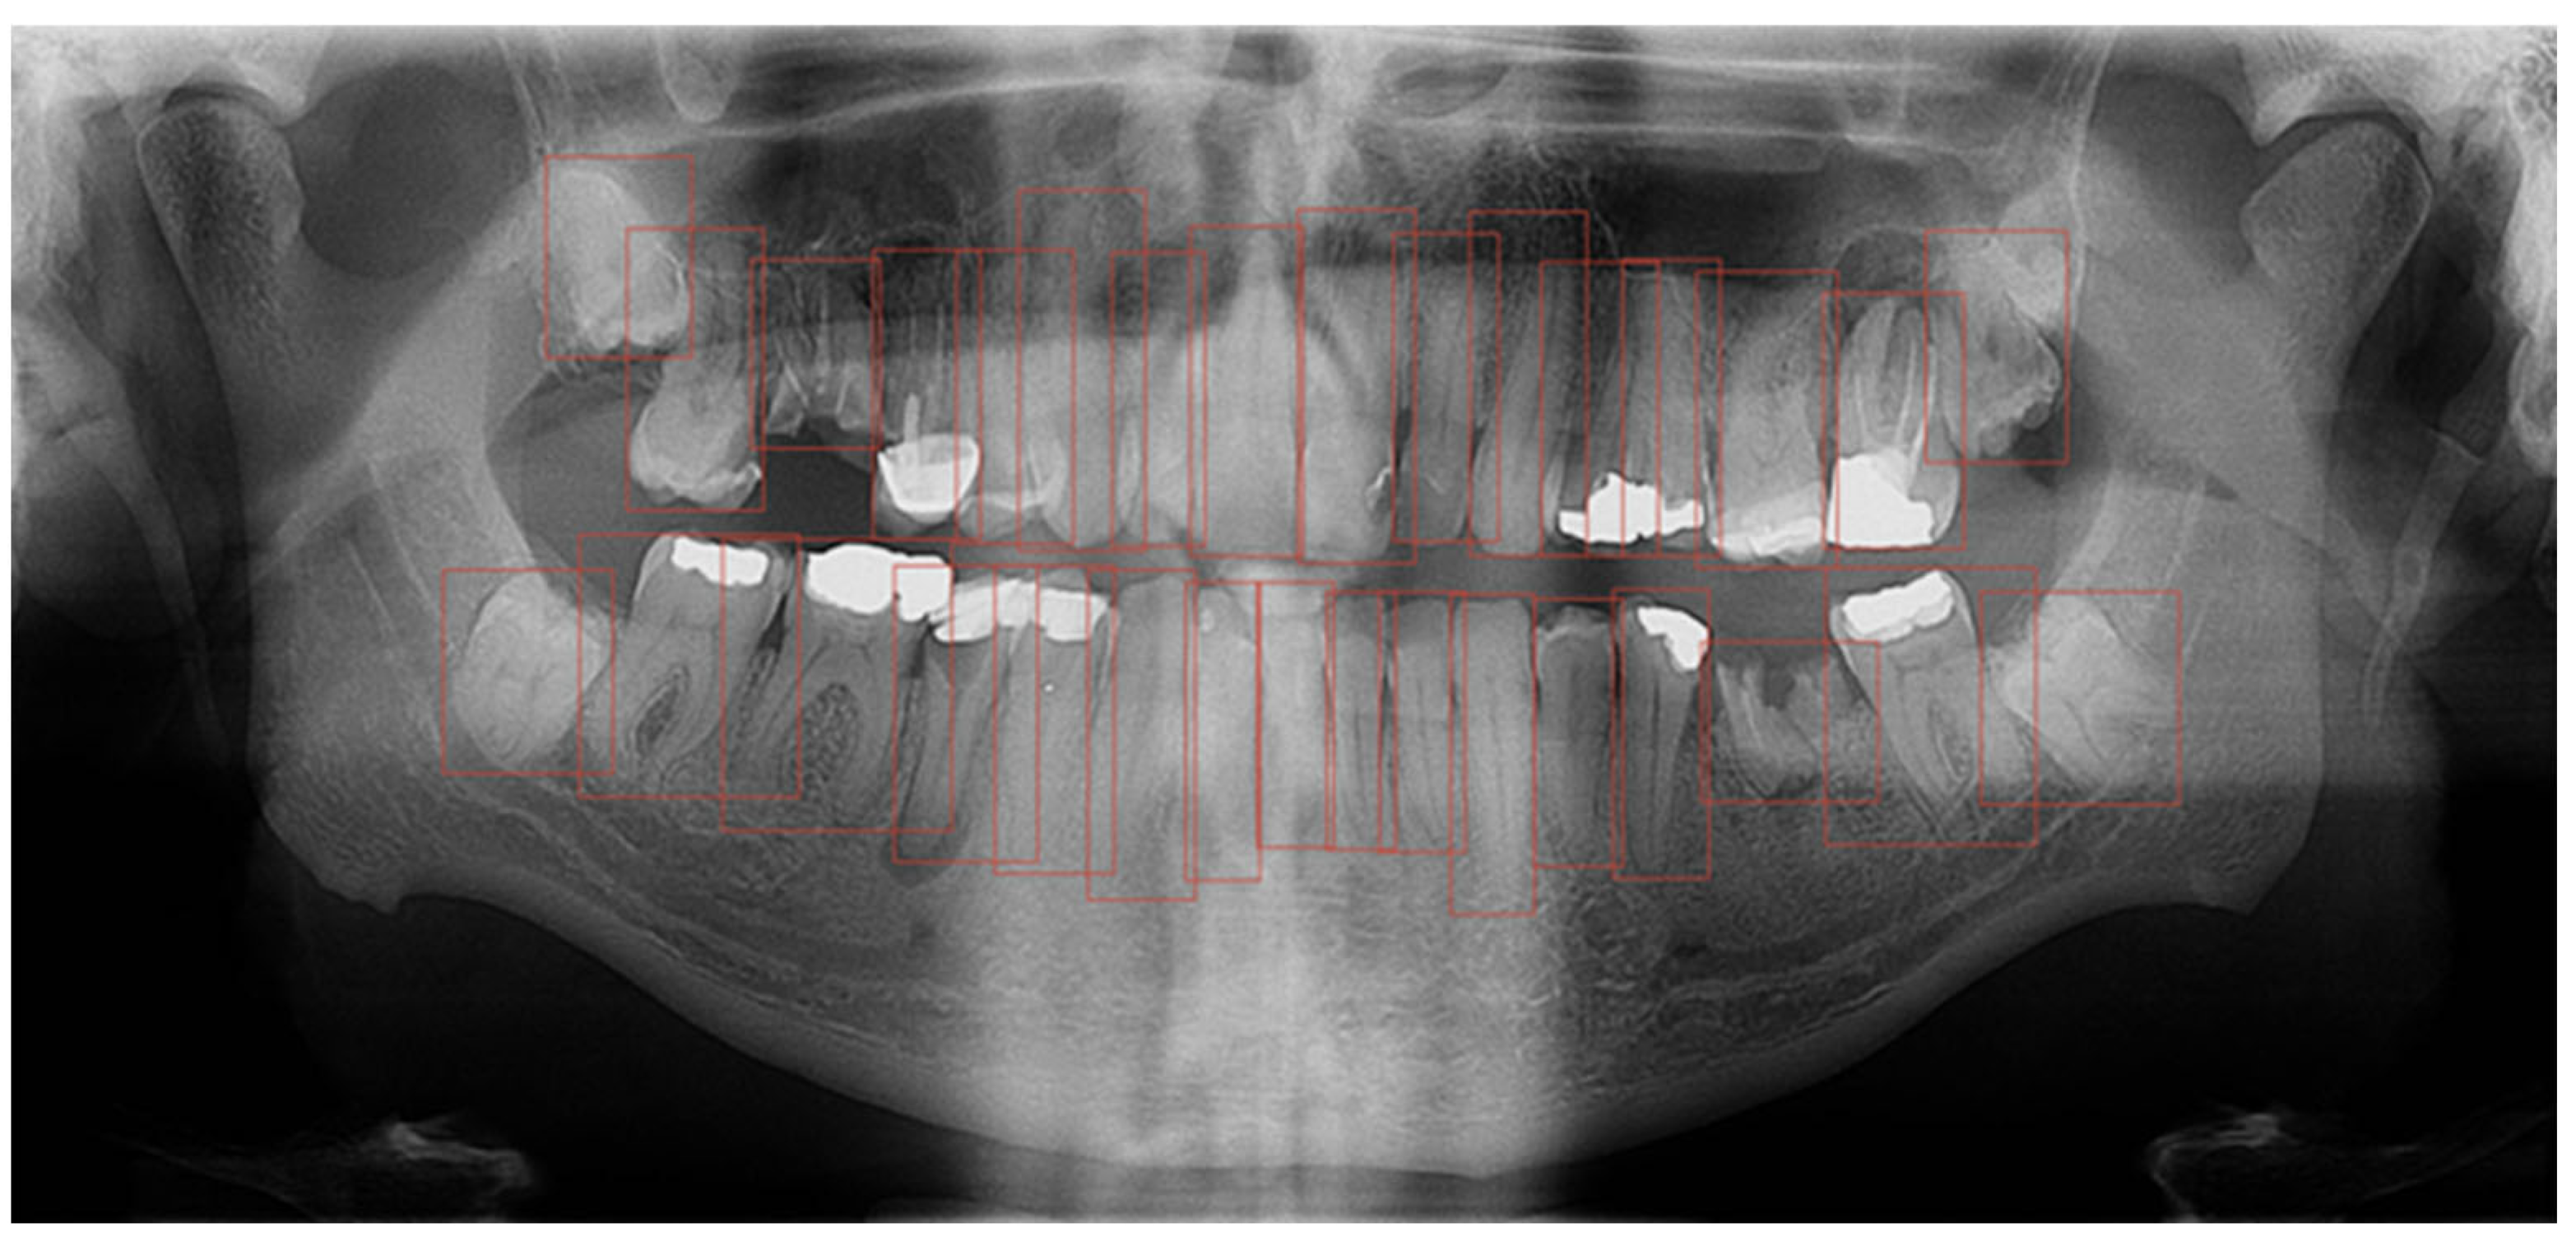

The computer program GIMP 2.10.22 was used to process the OPGs. GIMP is a powerful, free, and open-source image editor. The tool’s editing capabilities provided the annotators with a robust toolbox to adjust image parameters, helping them better discern the boundaries of the target regions. Importantly, the original OPGs were not modified during this process; everything except the annotated masks was discarded. Additionally, GIMP’s open format facilitated easy handling of per-pixel annotation data. Regarding annotation speed and validation, marking an entire tooth took about 10 min, while segmentation time depends on the number of interventions the tooth has undergone. For validation, we conducted multiple rounds of annotation-review iterations. Annotations were saved as XML files in the PASCAL VOC format for further use in neural networks. Every annotation step was conducted manually by a human expert; no annotations were automatically generated. Within the program, each tooth was outlined, covering the entire range of the tooth, including the crown and root (Figure 1). Teeth were labelled using the dual or binary system (FDI).

As a second layer, after outlining the teeth, each filling, crown, bridge, implant, endodontic filling, and tooth build-up was marked (Figure 2).

Furthermore, the findings were assessed across the complete OPGs, as well as in relation to segmented teeth (teeth separated from adjacent structures) and individual teeth. These individual teeth were marked in bounding boxes where the most prominent pixels were used as box margins (Figure 3).

A comparative analysis of these distinct methodologies was conducted to ascertain which approach produced the highest precision in tooth detection and segmentation. OPGs with manually marked teeth and dental interventions were used to train a CNN with the aim of automating tooth recognition and segmentation of dental procedures.

Figure 4. Workflow chart of the study design.